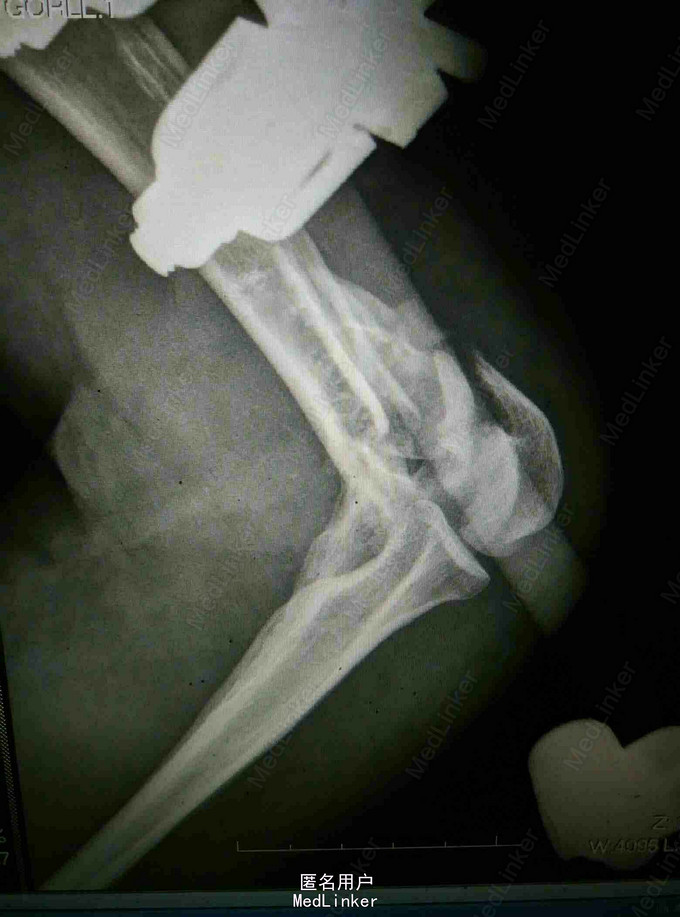

诊断:左肱骨髁间粉碎性骨折 左肘关节脱位 左迟神经 桡神经 正中神经损伤 治疗:左肘关节开放伤清创术+外固定架固定术

随访:术后继续抬高患肢消肿,行腕指功能锻炼,定期复查 讨论:患者骨折严重,涉及关节面及神经损伤,术后能恢复到什么程度不明确,既往有相似患者术后功能锻炼充分肘关节功能亦可得到良好恢复,想请教各位对固定方式选择的看法?